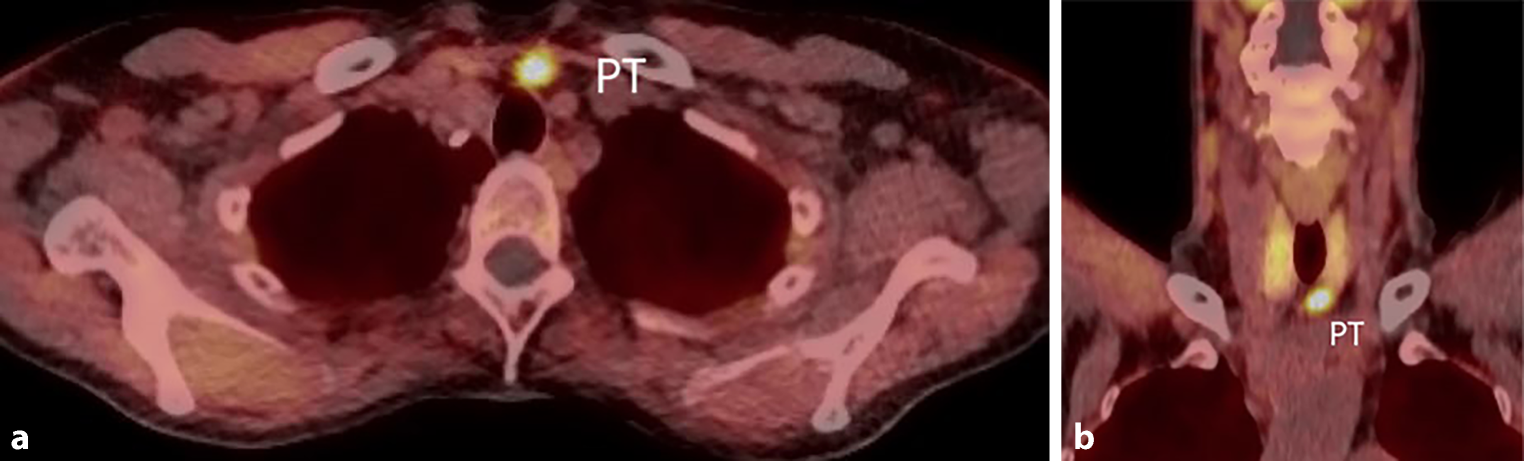

Instead of CT or MRI, 18F-fluorocholine PET was used in 4 patients, all of whom had positive results. 18F-fluorocholine PET is rarely available and expensive (Fig. 4). The FSD indicates the functional status of the suspected gland in combination with its localization, with a high sensitivity of up to 94% and an overall accuracy of 95% [2125].

Fig. 4

ab 18F‑choline positron-emission tomography scan of a left lower parathyroid adenoma in a 65-year-old female with primary hyperparathyroidism. PT Parathyroid adenoma